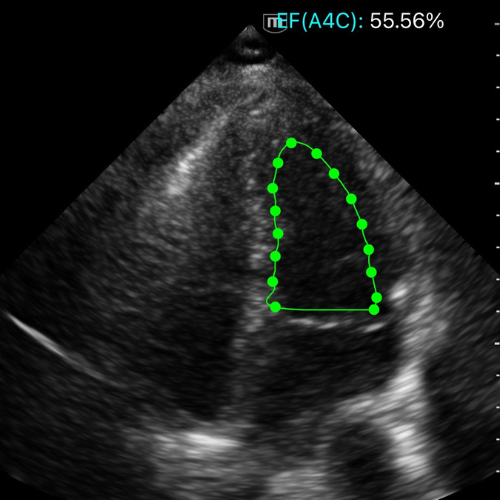

Apicale quatre cavités → estimation visuelle FEVG, calcul en méthode Simpson, MAPSE, onde S'

👀 Méthode visuelle

Observer la variation de volume du VG entre diastole et systole, et la vitesse du rapprochement des parois.

Un VG normal diminue d’environ un tiers de son diamètre à chaque battement :

- les parois se rapprochent harmonieusement,

- la cavité se vide presque complètement,

- le mouvement est vif et synchrone.

Quand la fonction baisse, la contraction devient lente, inégale, le VG reste dilaté, la valve mitrale s’ouvre peu et le volume résiduel systolique augmente.

Trois profils suffisent à la décision :

- Normale : cavité qui se vide franchement, parois toniques.

- Diminuée : contraction lente, cavité résiduelle importante.

- Très diminuée : parois quasi immobiles, volume constant.

![]()

Vue A5C avec FEVG normale.

Vue A4C avec FEVG diminuée.

Vue A4C avec FEVG très diminuée.